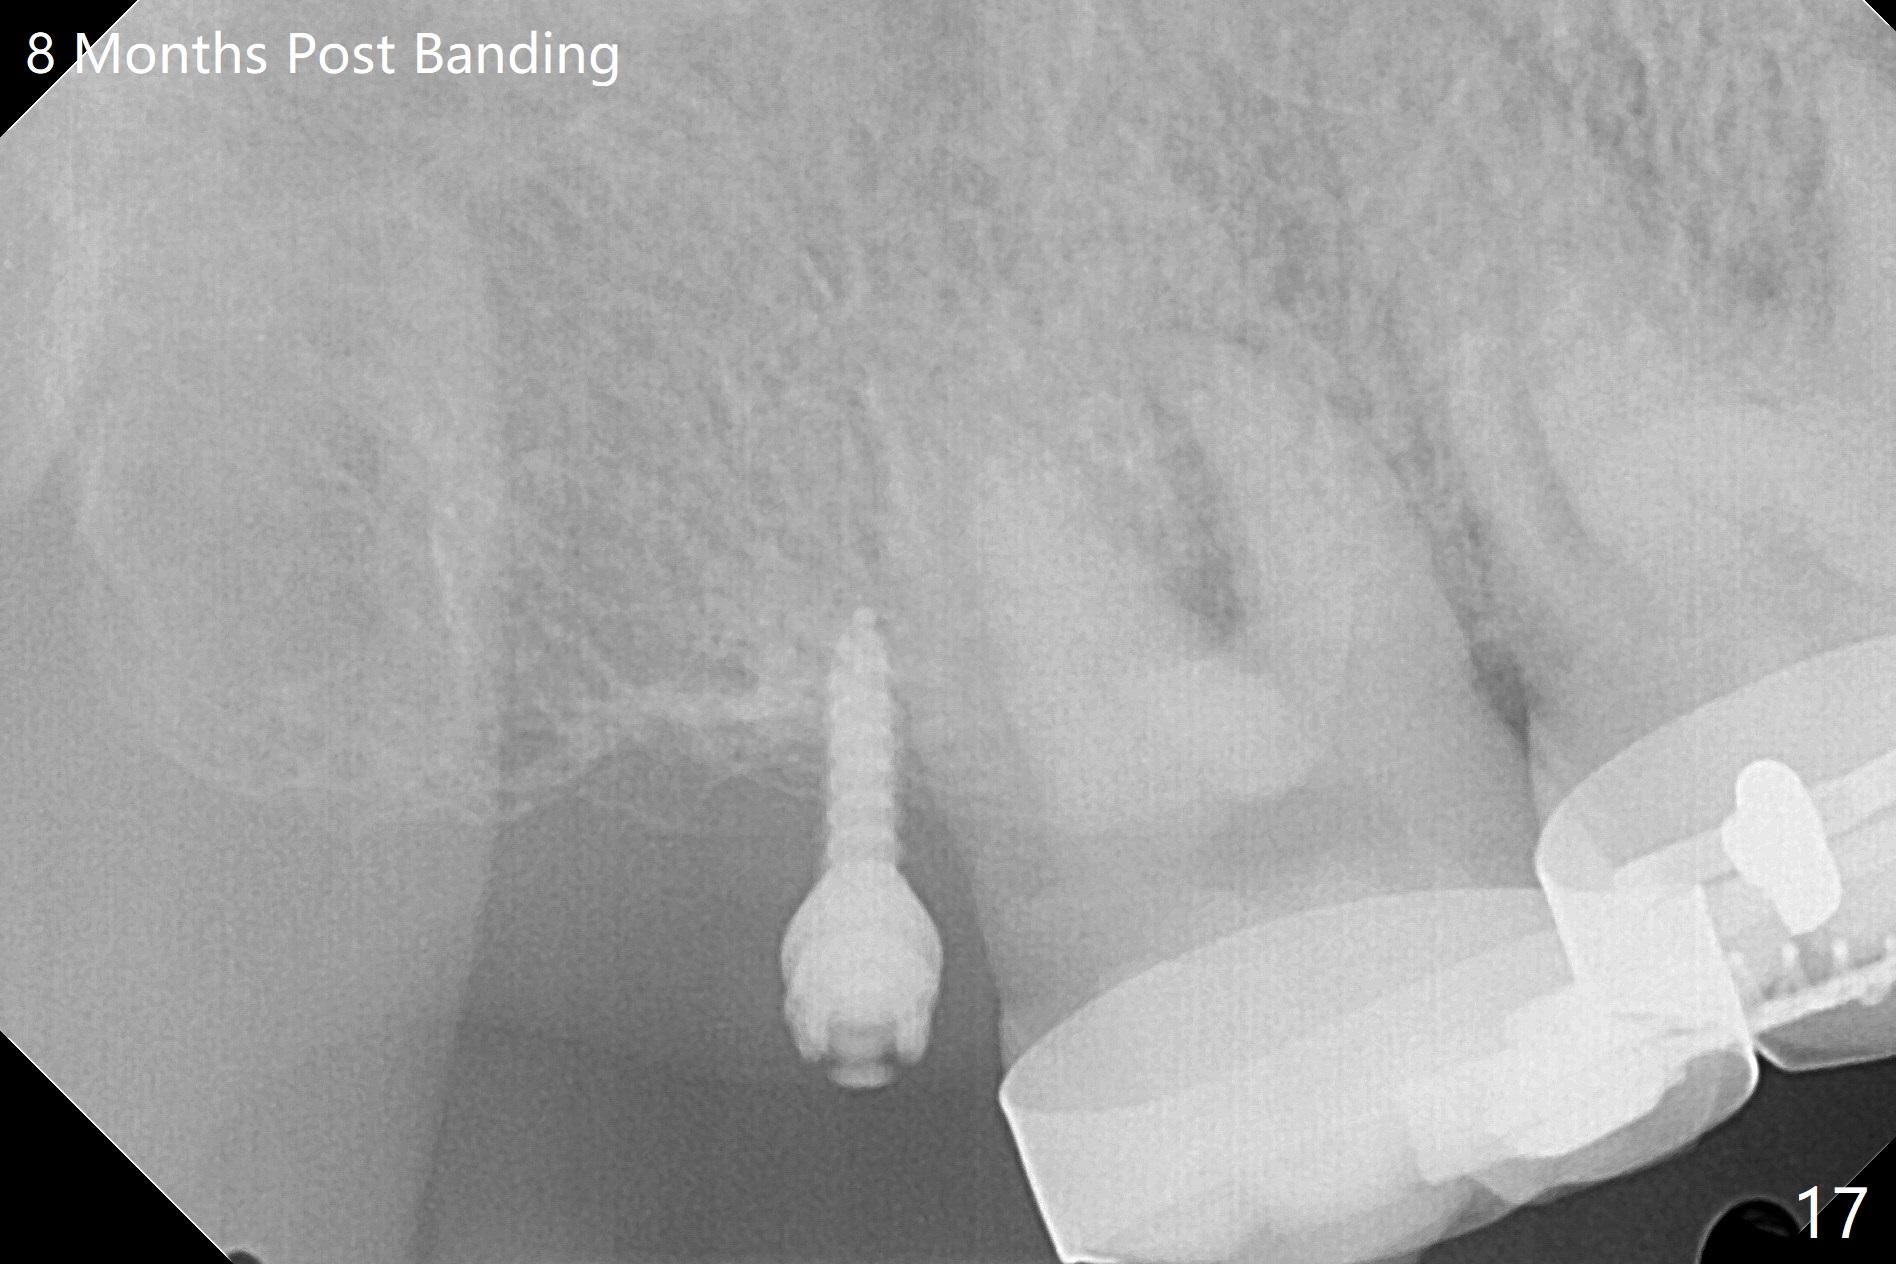

A 40-year-old man requests orthodontics after #17 and 32 extraction. UL5 is missing (Fig.1), while the upper midline deviates to the left (Fig.2 arrow) with crowding between UL2 and 3 (Fig.3). The main goal is to retract UL5 distal and move the upper midline to the right to alleviate UL anterior crowding. Implant will be not needed. To monitor potential root resorption associated with tooth movement, preop PAs are taken (Fig.4-7). The space for an implant at UR5 is narrow. UR4 needs to be distalized using UR7 or a miniimplant distal to UR7 as an anchor (Fig.8). UR4 and 3 will be repositioned to establish Class I occlusion (Fig.9). The space gained by UR4 distalization may be enough to correct the upper midline deviation and UL3 malposition (Fig.10). Brackets will be placed in the lower arch in spite of the normal alignment (Fig.11). UL2 and 3 brackets are unable to be engaged to 14 niti wire (Fig.12). Next visit try to engage UL2 bracket. If not, save the old wire for possible future reuse. Closed spring is placed with 18 ss wire <3 months post banding (coronavirus). Three weeks post closed spring between UR4-7, UR3,4 are being distalized (Fig.13). Distalization of UR4 is not much in 5.5 months (Fig.14,15). It seems necessary to use a miniimplant distal to UR7 as an anchor (Fig.16 white circle), place a long hook mesial to UL4 (more or less root movement instead of tilt) and place the same closed spring between the anchor and hook. In spite of the fact that UR4 seems to have been completely distalized and that UR2 is being distalized 8 months post banding (Fig.18), a 8 mm long mini-implant is placed in the maxillary tuberosity with minimal local anesthetic (Fig.17,19). A longer closed spring (18 mm) is placed between the implant and UR3 hook (Fig.20). Next appointment a lingual button will be placed at UR4 for rotation, while a post hook mesial to UR3 for torque. UR3 distalizes with the help of UR mini-implant, which is unfortunately loose. Next visit place lingual button at UR4 (Fig.21 arrow) to distalize the lingual cusp. Crimpable power hook is placed mesial to UR2 for distalization (for root torque, Fig.22). If it works, remove the wire and reposition the hook for UR1 next visit. UR2 is distalized in one appointment (~ 1 month, Fig.23, as compared to Fig.22). With lingual button at UR4, rotation seems to have been corrected shortly (Fig.24 arrow).